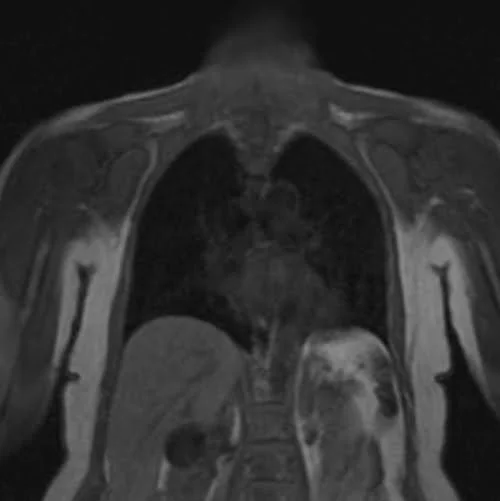

The care bolus image looks similar to the T1 localizer scans, with contrast in the blood vessels appearing bright during image acquisition.

CARE BOLUS SEQUENCE USED IN CHEST ANGIOGRAPHY